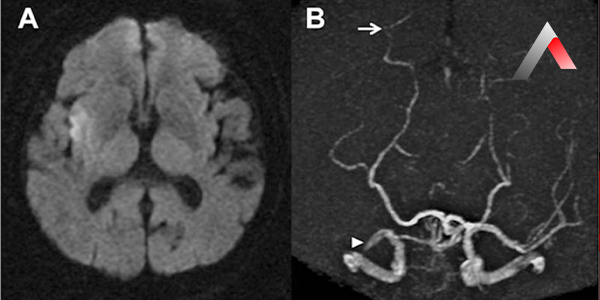

Beyin Damar Tıkanıklığı Nasıl Teşhis Edilir?

Beyin damar tıkanıklığı teşhisi için aşağıdaki yöntemler kullanılır:

• Bilgisayarlı tomografi (BT) anjiyografi: Beynin detaylı görüntülerini elde etmek ve tıkanıklığın yerini ve boyutunu belirlemek için kullanılır.

• Manyetik rezonans anjiyografi (MRA): BT anjiyografiye benzer şekilde beyin damarlarının ayrıntılı görüntülerini sağlar.

• Dijital subtraksiyon anjiyografi (DSA): Kasıktaki bir atardamardan ince bir kateterin beyne kadar ilerletilerek kontrast madde verilmesi ve röntgen çekilmesiyle yapılan bir işlemdir. Tıkanıklığın detaylı değerlendirilmesi için kullanılır.